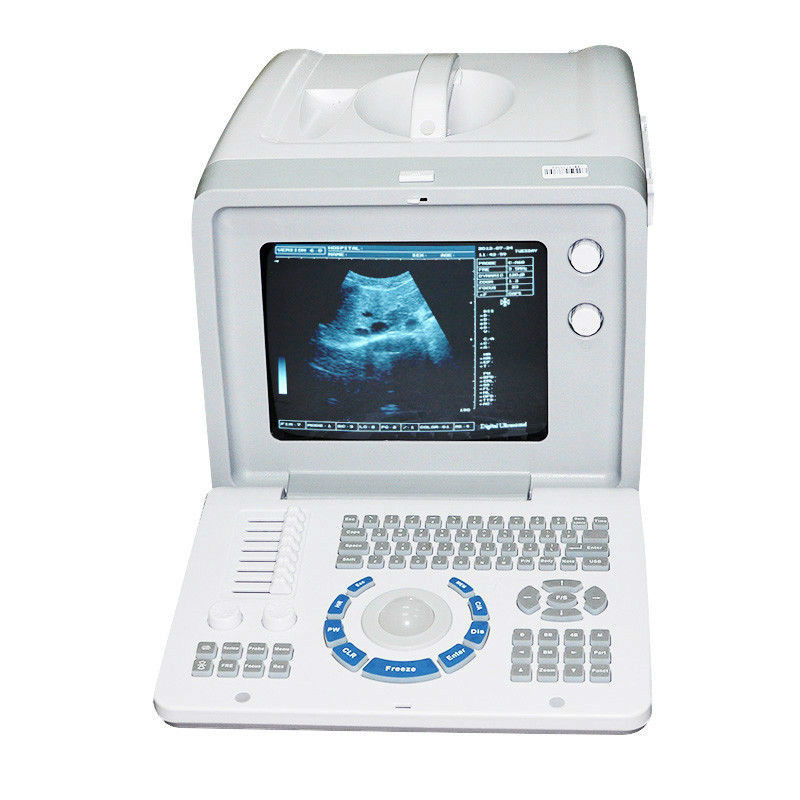

State-of-the-Art Imaging Technology

The Diagnostic Ultrasound Scanner is an advanced medical device that uses high-frequency sound waves to create precise images of the body's internal structures. This technology plays an important role in diagnostics because it helps healthcare professionals identify issues such as abnormalities in organs and tissues, leading to early intervention. The incorporation of a Convex and Transvaginal Probe offers versatility, making it suitable for various examinations. Using this ultrasound scanner, doctors can provide better care and ensure patient satisfaction.

Enhanced Visualization with 3D Imaging

One of the standout features of the Diagnostic Ultrasound Scanner is its 3D imaging capability. This feature allows for comprehensive views of anatomical structures, which is critical for accurate diagnosis. Patients benefit from clearer images that assist in identifying conditions that may not be visible with traditional 2D scans. Therefore, the scanner enhances diagnostic confidence, helping practitioners make informed decisions regarding treatment plans. Additionally, the engaging 3D visuals can facilitate discussions with patients about their health.

User-Friendly Interface for Efficient Workflow

The Diagnostic Ultrasound Scanner is designed with an intuitive interface, ensuring that both novice and experienced users can operate it with ease. This user-friendly setup reduces learning curves and minimizes errors during examinations, making it more efficient in a fast-paced medical environment. Moreover, quick access to various imaging modes and settings allows practitioners to focus on patient care without unnecessary delays. Thus, the combination of technology and usability significantly improves overall efficiency in medical practices.